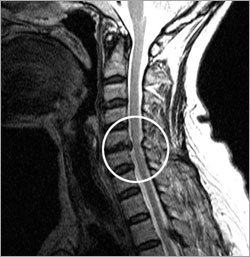

颈椎间盘突出症是颈椎之间的椎间盘突出压迫周围神经的病症。如果后颈的疼痛或麻的感觉沿着神经影响到肩部和手臂,就应该考虑是否患上了颈椎间盘突出症。

最重要的判定标准是看是否压迫了中枢神经。如果突出的椎间盘严重压迫中枢神经,则使人难以入睡等非常痛苦。在这种情况下,即使是轻轻摔倒,也有可能导致全身瘫痪,所以需要进行手术治疗。

虽然椎间盘压迫了中枢神经,但是也有疼痛或麻的感觉较轻的情况。根据医生的判断,一般有两个治疗方案,一是必须立即手术治疗,二是接受物理治疗的同时进一步观察。应该充分地研究压迫神经的程度和症状以及手术的安全性,然后再决定是否进行手术。

椎间盘只压迫末梢神经的情况,大部分采取药物治疗和物理治疗双管齐下的方法。但即使是只压迫了末梢神经,但如果压迫程度严重,手和胳膊的感觉迟钝,而且变得无力,也应考虑接受手术治疗。